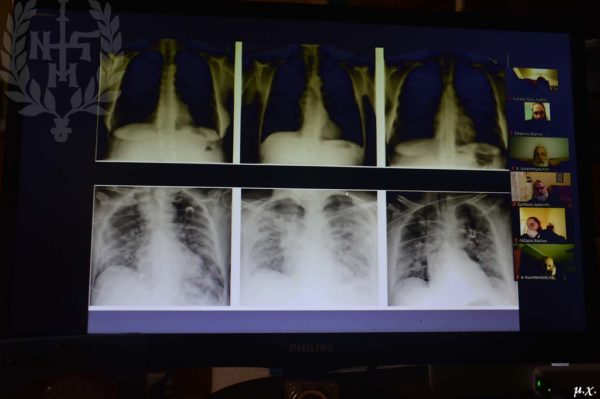

- Τριαντάφυλλος Γερούκης, Ακτινολόγος, Συντονιστής Διευθυντής του Ακτινολογικού Τμήματος του Γενικού Νοσοκομείου «ΠΑΠΑΝΙΚΟΛΑΟΥ». Θέμα: Ακτινολογική προσέγγιση της COVID.